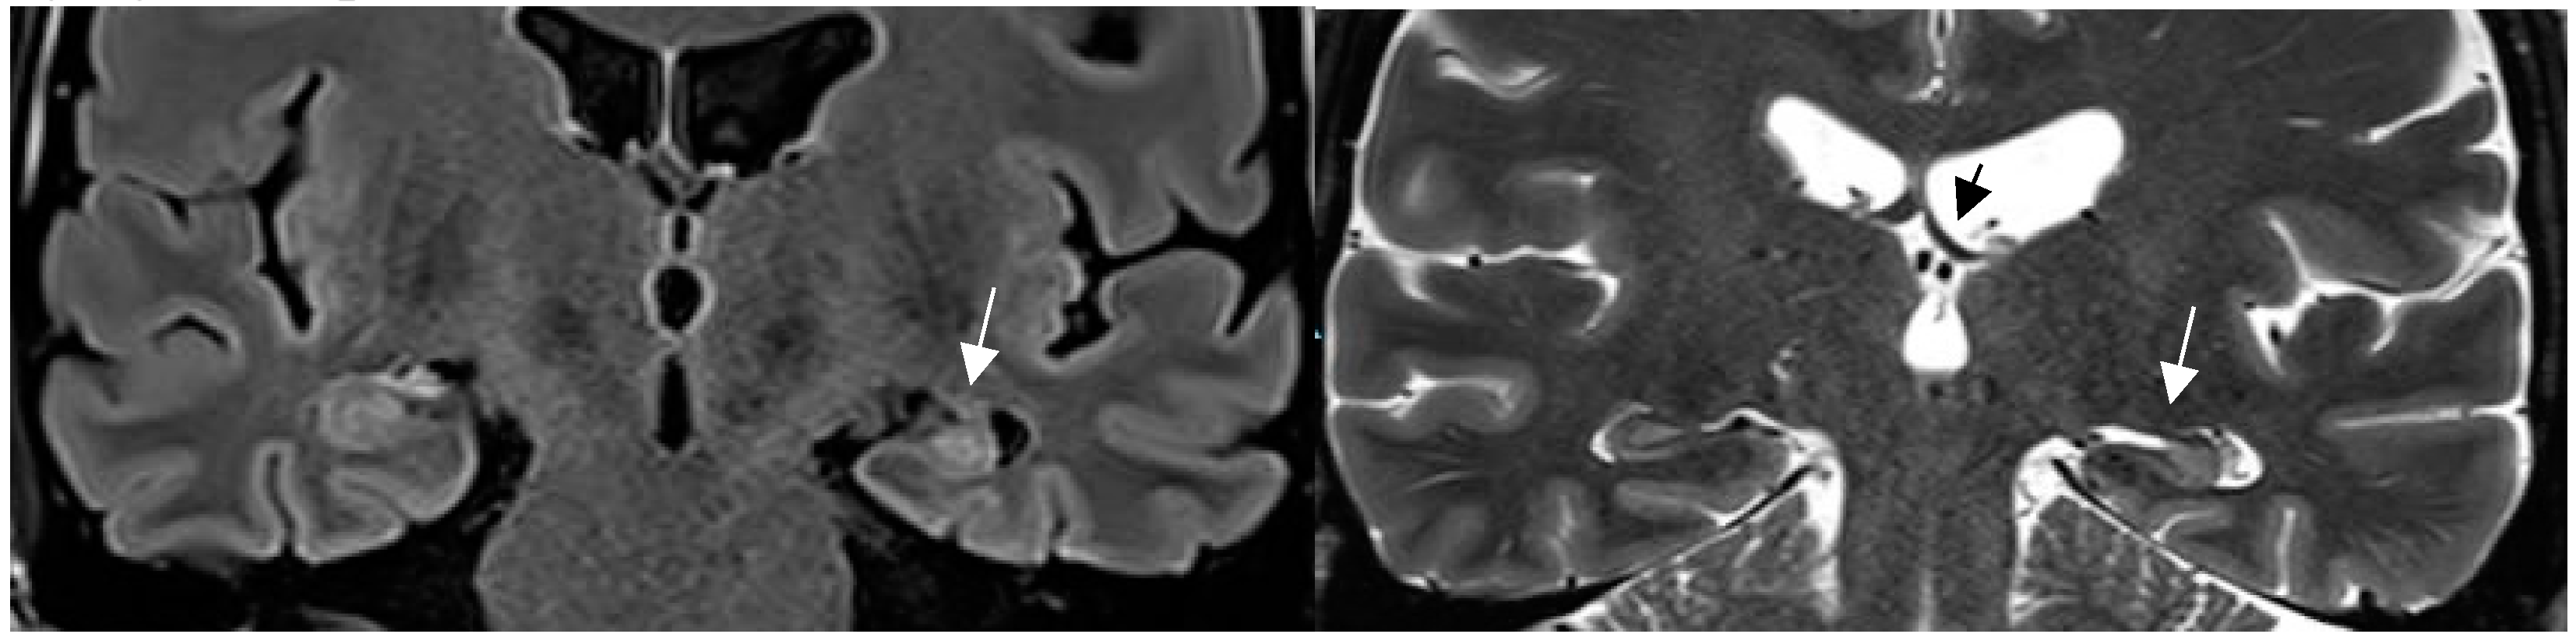

4.1. Pathologies Likely to Be Missed on Brain MRI in Patients with Epilepsy

4.2. A standardized Epilepsy Specific Protocol Provides Superior Diagnostic Yield

4.3. Expert Readers Take Advantage of the Added Value of an Epilepsy Specific Protocol

4.4. Increased MRI Field Strength and Receive Coils Improve Lesion Recognition by Enhanced Signal and Spatial Resolution

4.5. New MR Sequences Display Tissue Properties for Improved Visualization of Lesions

4.6. Postprocessing by Morphometric Analysis Improves Focal Lesion Detection Beyond Visual Analysis

4.7. Postprocessing by Quantitative Analysis of Signal Intensity, Volumetry Enhances Temporal Lesion Identification

4.8. Postprocessing by 3D Surface Rendering Technique to Improve Comprehension of Superficially Located Lesions

4.9. MR Fingerprinting Exploits Tissue Properties to Reflect “Activity“ of a Lesion

4.10. MR Perfusion Exploits Blood Flow to Identify Interictal Laterality of a Focus

4.11. Contrast Administration Is of Limited Gain with Respect to Lesion Detection But May Contribute to Characterization of an Abnormality

4.12. New Entities: Knowledge Shapes Perception